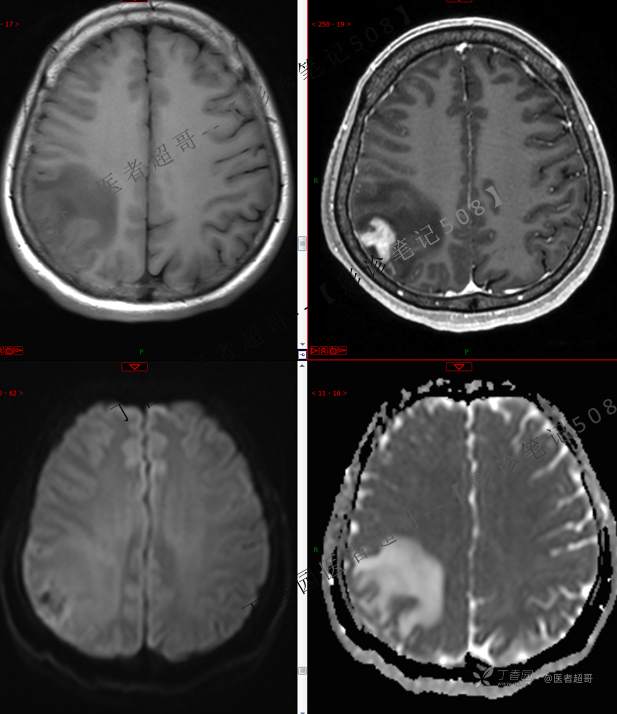

【影诊笔记508】同病异影,个人感觉有难度,欢迎分析,领丁当!有详细术程及病理!

患者性别:女

患者年龄:46岁

主 诉:突发一过性意识不清伴肢体抽搐5天余。

现病史:患者5天余前无明显原因及诱因出现一过性意识不清,伴肢体抽搐,持续约2-3分钟,后意识逐渐恢复,无明显头痛头晕,无恶心呕吐,无肢体抽搐,无呼吸困难,无二便失禁,后就诊于当地医院,行颅脑CT示“颅内占位性病变”,予以药物对症治疗,具体不详,门诊以“颅内占位性病变”,收入我科。患者自发病以来,未进饮食,近期体重无明显变化。